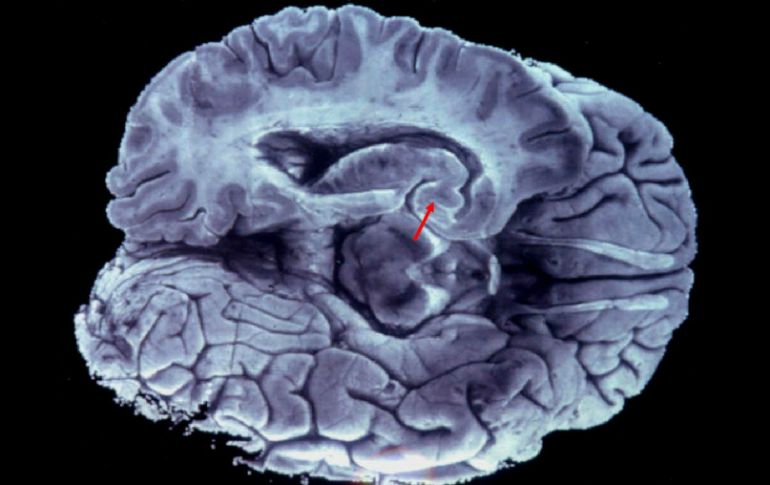

Tecnología | Científicos de Tanaka identifican sustancia en aquellos que tienen el padecimiento Crean tecnología para detectar antes el Alzheimer El equipo de científicos del Nobel Tanaka logran identificar pequeñas cantidades de una sustancia que se encuentra en la sangre de los tienen el padecimiento Por: EFE 27 de marzo de 2013 - 09:45 hs Hasta ahora a los pacientes se les sometía a pruebas mediante instrumental de Tomografía por Emisión de Positrones. EFE / TOKIO, JAPÓN (27/MAR/2013).- El equipo de científicos de la empresa nipona Shimadzu, liderados por el Premio Nobel de Química en 2002 Koichi Tanaka, ha desarrollado una tecnología capaz de acelerar el diagnóstico para los casos de Alzheimer. A través del nuevo instrumental, los investigadores han logrado detectar pequeñas cantidades de una sustancia que se encuentra en la sangre de los enfermos de Alzheimer, informó hoy el diario Nikkei. El equipo del ingeniero Tanaka logró este avance a través de mejorar la precisión de la tecnología de espectrometría de masas, lo que permite detectar en la sangre la acumulación de proteínas beta-amiloide, una de las probables causas del Alzheimer al afectar la transmisión entre las células nerviosas del cerebro. Según las investigaciones, esta proteína se acumula en el cerebro durante un periodo de entre 10 y 15 años antes de que aparezcan los primeros síntomas de la enfermedad. Al margen de situarse en el cerebro, esta proteína también se acumula en la sangre, aunque en cantidades tan sumamente pequeñas que su identificación resulta muy compleja a través de los ensayos habituales, algo que con la tecnología descubierta por el equipo de Tanaka sí será posible. Hasta ahora a los pacientes se les sometía a pruebas mediante instrumental de Tomografía por Emisión de Positrones, PET, o a través de extraer muestras de líquido cefalorraquídeo, dos procedimientos complejos y dolorosos. La nueva técnica descubierta por el equipo de Tanaka entrará ahora en fase de pruebas en colaboración con el Centro Japonés de Geriátricos y Gerontología. Con estos ensayos, se espera que el equipo logre determinar la relación entre la cantidad de proteína beta-amiloide presente en la sangre y la aparición de la enfermedad, lo que permitiría anticipar el diagnóstico y crear nuevos tratamientos. El científico japonés, nacido en Toyama en 1959, recibió el Nobel de Química 2002, junto con el estadounidense John Fenn y el suizo Kurt Wüthrich, por sus trabajos sobre las macro-moléculas biológicas. Temas Premios Nobel Ciencia médica Alzheimer Lee También Osmar Olvera, nominado a Atleta del Año por World Aquatics El “malabarista” de la Casa Blanca Nominados de los MAMA Awards 2025 y cómo votar por tu favorito Estudio chino revela una mutación que eleva riesgo de alzhéimer Recibe las últimas noticias en tu e-mail Todo lo que necesitas saber para comenzar tu día Registrarse implica aceptar los Términos y Condiciones